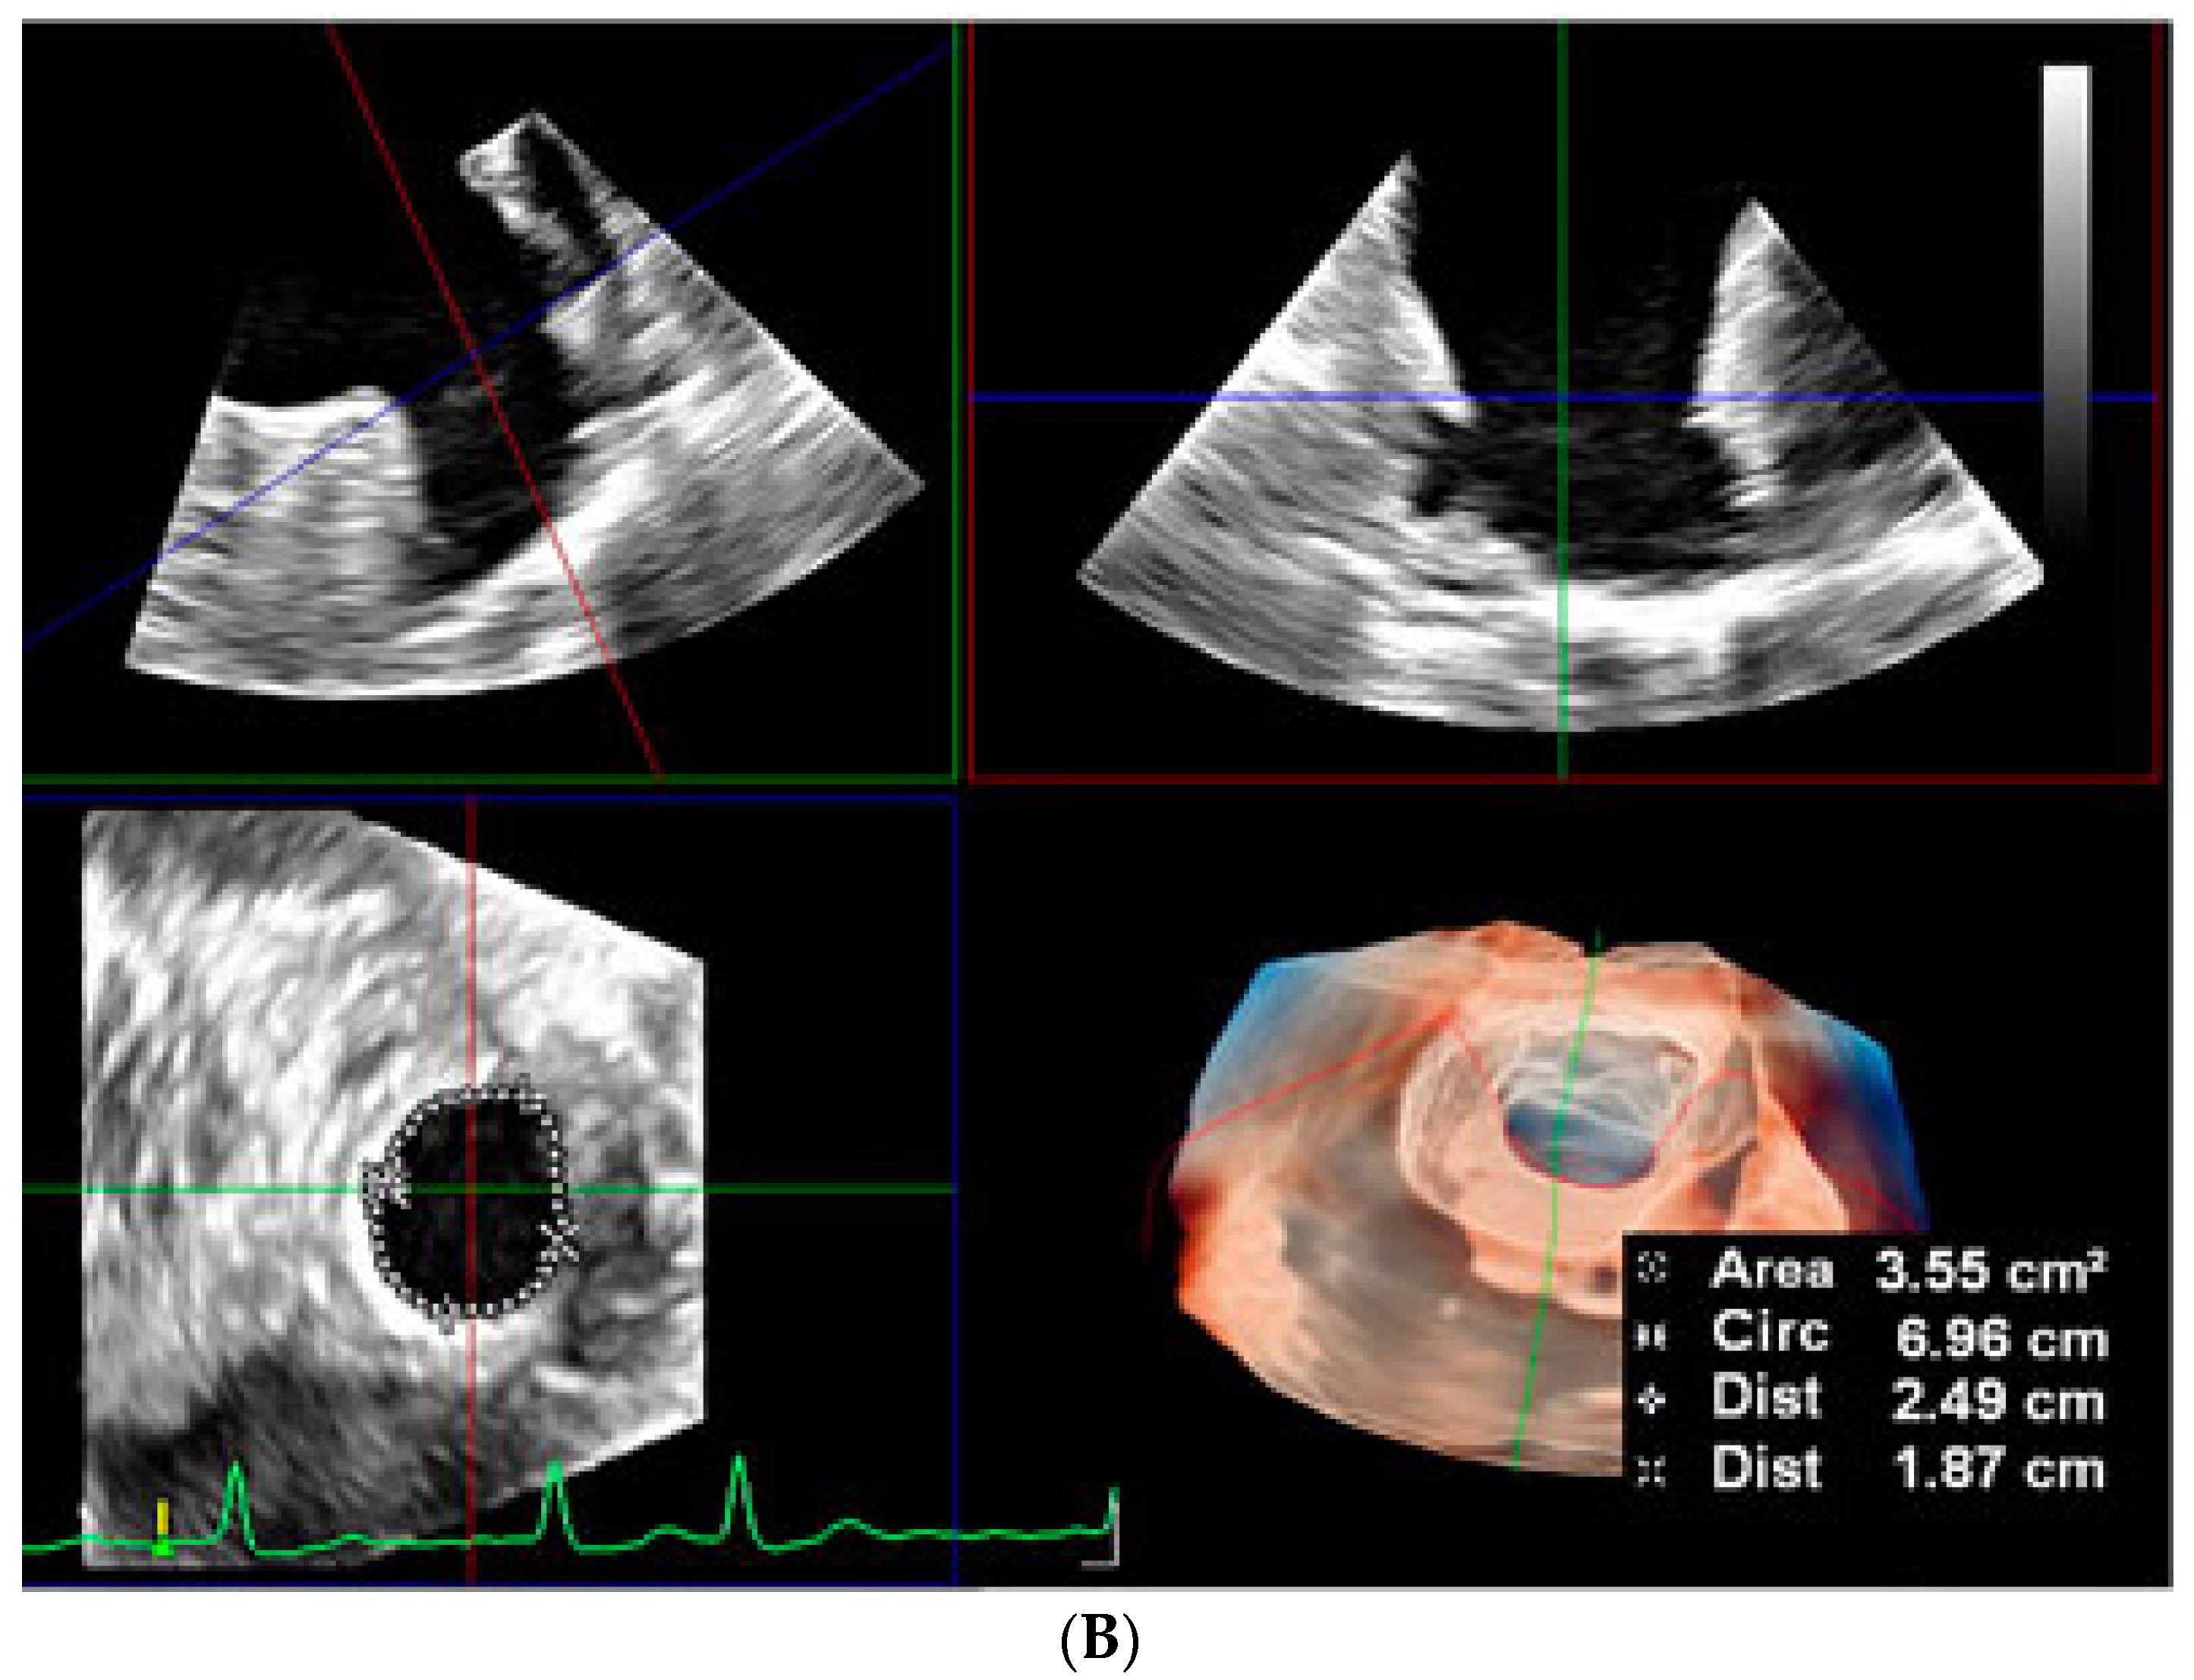

2.2.2. LAA Measurements (Anatomy and Morphology)

2.2.3. Intra-Procedural TOE